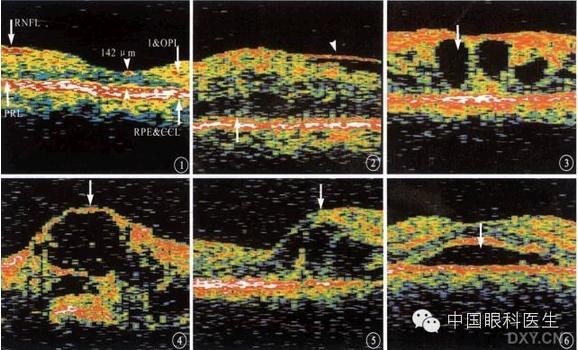

1、正常视网膜OCT图像:最高反射层面;最低反射层面;中等反射面;中心凹图像。

2、眼底异常结构的OCT影像:视网膜厚度改变 (如 变薄、 变厚);光反射改变(如反射增强、反射减弱、无反射)。

3、中浆:神经上皮脱离( 神经上皮与色素上皮间是无反射的暗区);色素上皮脱离(色素上皮光反射带隆起,其下方是无光反射的暗区;必须存一端和色素上皮反射带相连;均可测量出神经上皮脱离和色素上皮脱离区范围、高度)

神经上皮脱离

神经上皮、色素上皮脱离

4、视网膜前膜:前膜和视网膜的关系(距离和粘连);前膜的厚度;黄斑假性裂洞

5、黄斑水肿:海绵状无反射区;囊样无反射区;视网膜神经上皮脱离。

神经上皮脱离及囊样无反射区

6、板层黄斑裂洞:在裂洞底部仍可见到部分神经上皮及色素上皮的反射。

板层裂洞伴神经上皮脱离

7、全层裂洞:神经上皮层全层无反射,只见洞底色素上皮层反射。